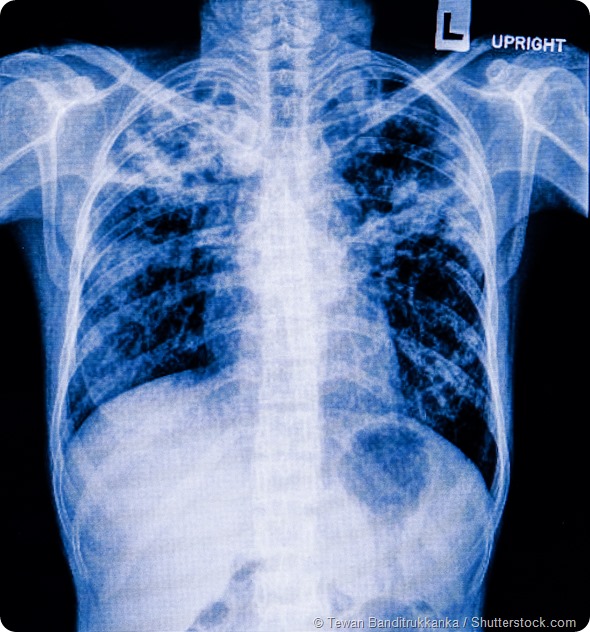

Can you give me a brief overview of bacterial lung infections and why they are so lethal?

If you trace back to the largest pandemics in human history, for example the Spanish Flu, the number of deaths was around 40 million. For flu to truly have an epidemic or pandemic potential, the lethality of the infection itself can't be so high that it doesn't allow for transmissibility. If the flu virus is too lethal than it has a harder time spreading from host to host.

When scientists first started to look at what happened during the 1918-1919 pandemic, what we saw was that the major cause of death was not the flu virus but that patients died due to a secondary bacterial pneumonia. So the major question became what was the 1918 flu strain doing that caused people to become susceptible to bacterial super-infections?

So scientists began digging patient samples from the Alaskan permafrost. What they observed was that the primary flu infection caused a significant amount of lung damage in the host without killing them, which then allowed streptococcus pneumonia, the common bacterial super infection, to grow in the lung and cause systemic infection. The body becomes unable to combat this bacterial super infection, which becomes the primary cause of mortality.